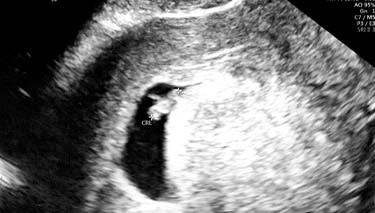

The ultrasound will pick up images of your baby's organs in a series of cross sections. This can be confusing at first, until you become used to the images and your eyes adjust. Your baby's bones will be white on the screen and the amniotic fluid will appear as black. Their tissues will be grey and have a speckled appearance.

- Measurements of your baby's head, biparietal diameter, length and a measurement of their femur (long bone in the thigh) will also be taken. These measurements are compared with the average for babies of the same gestation.